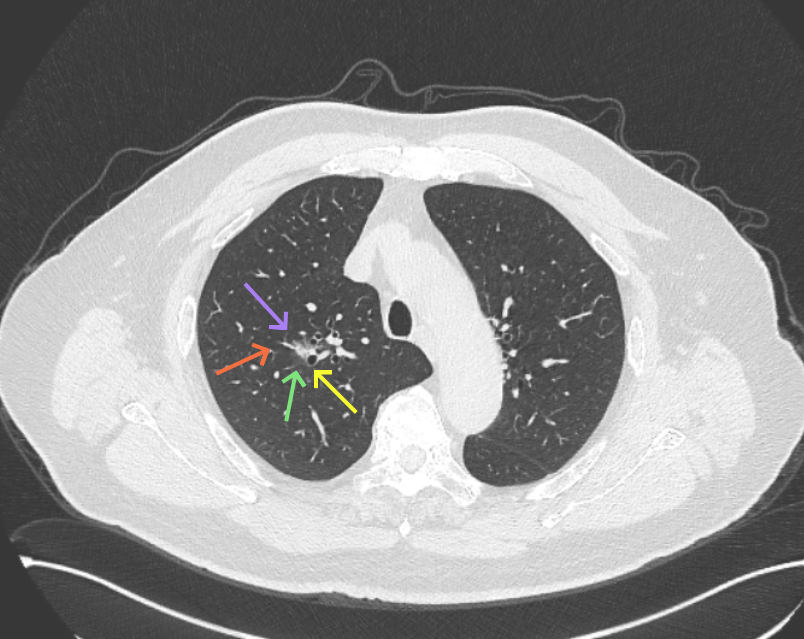

但病灶B却显然进展!变成以实性成分为主的了!

再看病灶B的2026年3月细节影像特征:

边缘位置也是较淡的磨玻璃成分。

上图是混合密度,轮廓较清,瘤肺边界欠清晰。

病灶A以及他处磨玻璃结节其实进展都是不明显的,略与2022年比,病灶A稍显明显点。病灶B开始时极淡,之前进展虽有但也甚微,直到2025年9月仍是磨玻璃成分为主,只是点状少许密度稍高成分。但在最近半年内却显然进展!若从影像上判断,基本上就得是浸润性腺癌了。那有几点:一是必不能再随访;二是大小来看仍是1A期;三是从快速进展来说,可能含有部分高危亚型,比如微乳头或实体型等;四是他处的磨玻璃结节以及病灶A显然不能用病灶B的转移来解释,仍考虑是多原发早期肺癌。

结友问能否先穿刺?我是这么考虑的:你这个病灶B一是位置深,且靠近附近的血管,不容易穿刺;二是从影像变化来看,基本上肯定是恶性的,不是100%,也是95%以上的概率。刚才我又在重建看冠状位与矢状位以及各次影像,目前混合密度的其实是后来者居上,原来刚开始是它比旁边的病灶密度淡的,但它的密度不是太纯,前次你自己也说似乎有点状偏实性成分。只是最近这半年进展特别快。这说明它的恶性程度较它边上原来就比较明显的那处恶性程度高,亚型中大概率有低分化的成分。所以从目前的影像来看,要尽快手术,而且切肺叶更为稳妥些。